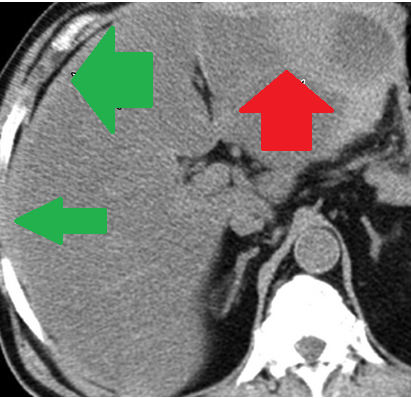

Αριστερό περινεφρικό αιμάτωμα και δεξιό αιμάτωμα λαγονοψοΐτη — αντιπηκτική αγωγή (Ευγενική παραχώρηση Dr. V. Penopoulos)